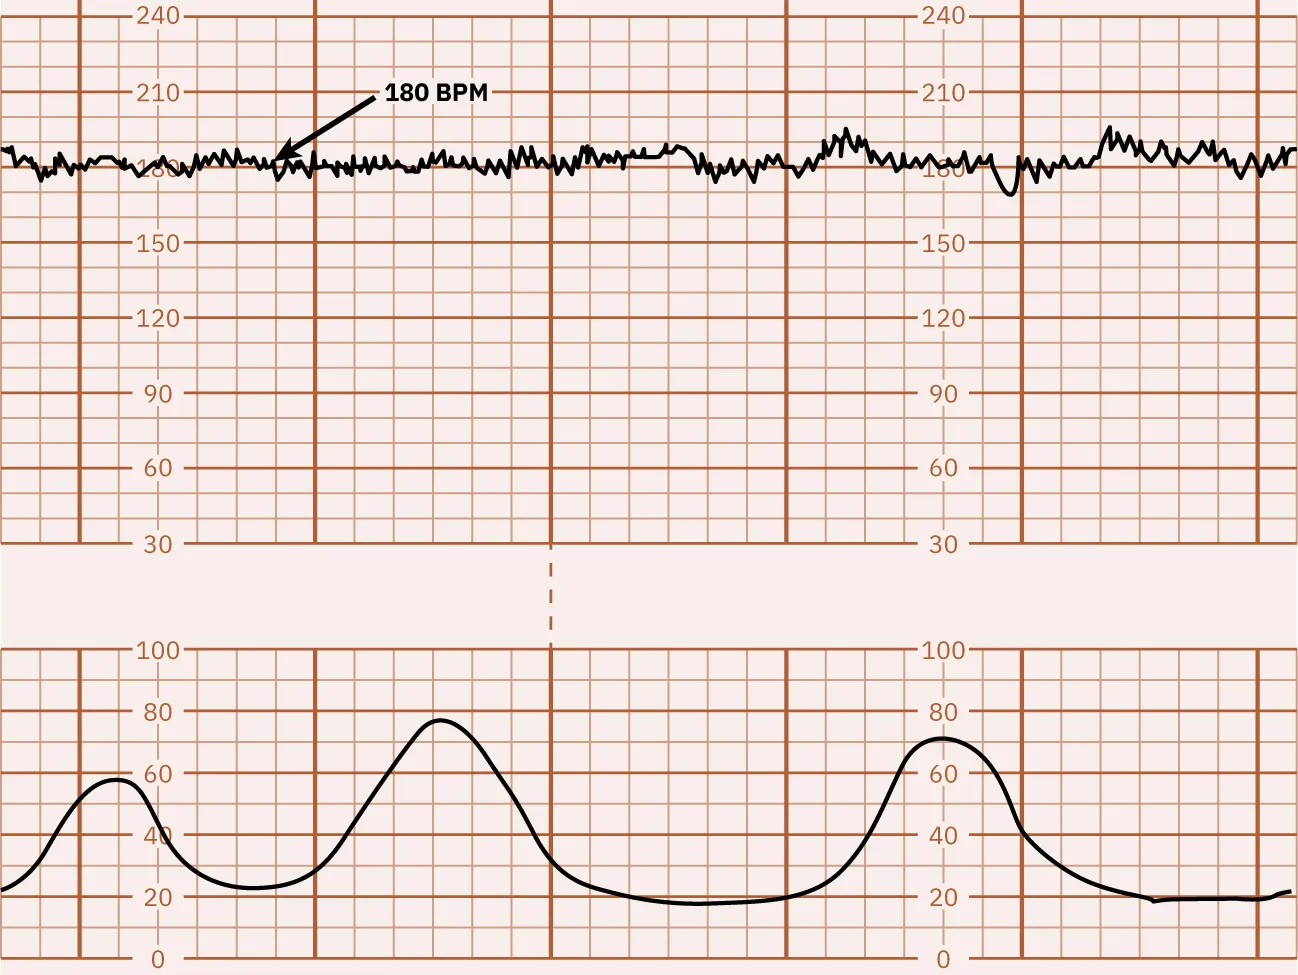

A FHR baseline fluctuation greater than 25 bpm is considered marked FHR variability. Because of the extreme fluctuations, the FHR baseline is undeterminable. Marked FHR variability suggests hypoxia and is usually seen during the second stage of labor. Marked variability requires further assessment to determine the cause and notification of the health-care provider. Figure 16.8 shows a monitor tracing that indicates marked variability.

Fetal heart rate reading indicating marked variability.

Figure 16.8 Marked FHR Variability This monitor tracing shows marked FHR variability with greater than 25 bpm. (attribution: Copyright Rice University, OpenStax, under CC BY 4.0 license)